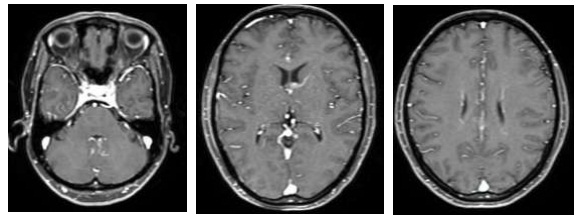

- Chụp cắt lớp vi tính ngực:Khối vùng rốn phổi phải gây xẹp phổi kích thước 28x32mm. Dịch khoang màng phổi phải dày 50mm. Khống thấy hạch to trung thất

So sánh hình ảnh cắt lớp vi tính ngực trước và sau điều trị 3 chu kỳ:

- Chụp cắt lớp vi tính ngực:Giảm thể tích phổi phải, tổn thương đông đặc thùy dưới phổi phải, dịch màng phổi phải dày 6mm.

Sau 6 chu kỳ điều trị:

Sau điều trị hoá trị kết hợp Pembrolizumab cho thấy: U phổi giảm kích thước, hạch trung thất không còn, chất chỉ điểm khối u CEA, Cyfra 21-1 giảm về giới hạn bình thường, tổn thương di căn gan các nốt nhu mô gan giảm bớt. Bệnh nhân không gặp tác dụng phụ đáng kể nào trong quá trình điều trị.